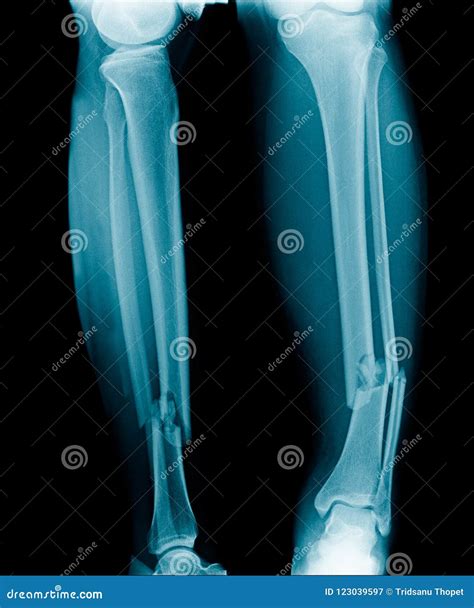

The leg consists of three primary long bones: the femur (thigh bone), the tibia (shin bone), and the fibula (the smaller bone on the outside of the lower leg). Fractures of the leg can occur in any of these bones depending on the mechanism of injury. These breaks are generally categorized based on the severity and the type of bone disruption:

• Stable fracture: The broken ends of the bone line up and are barely out of place.

• Displaced fracture: The bone ends are misaligned and may require manual manipulation or surgery to realign.

• Comminuted fracture: The bone shatters into three or more pieces.

• Compound (Open) fracture: The bone breaks through the skin, carrying a high risk of infection.